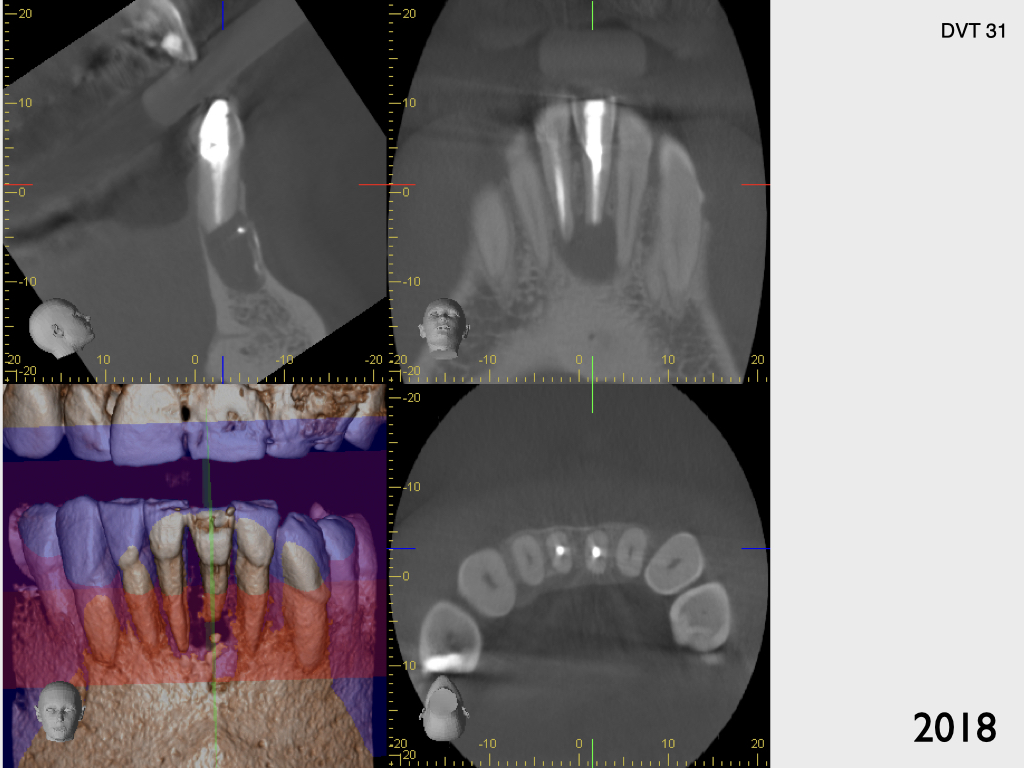

Und wieder ein UK Frontzahn